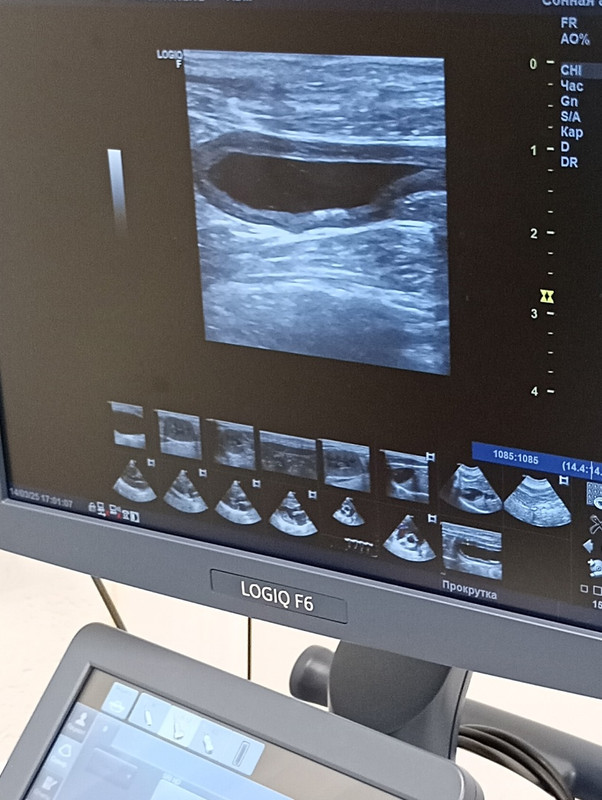

УЗИ мочевого пузыря 14.02.2025

УЗИ мочевого пузыря 14.03.2025